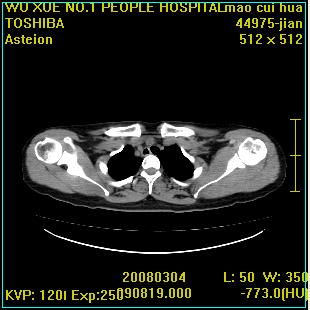

标题: CT12025:男,50岁,左肩活动受限半年。 [打印本页]

标题: CT12025:男,50岁,左肩活动受限半年。

肩关节骨质破坏呈小囊状,其周软组织轻度肿胀,余未见异常。

考虑:肩袖损伤。建议mri。

左侧肱骨头密度不均匀,高低混杂,周围软组织略肿胀,考虑结核性病变。

左侧肱骨头密度不均匀,高低混杂,髓腔密度稍高,周围软组织略肿胀,肌间隙模糊,考虑慢性骨髓炎可能。密切结合临床!